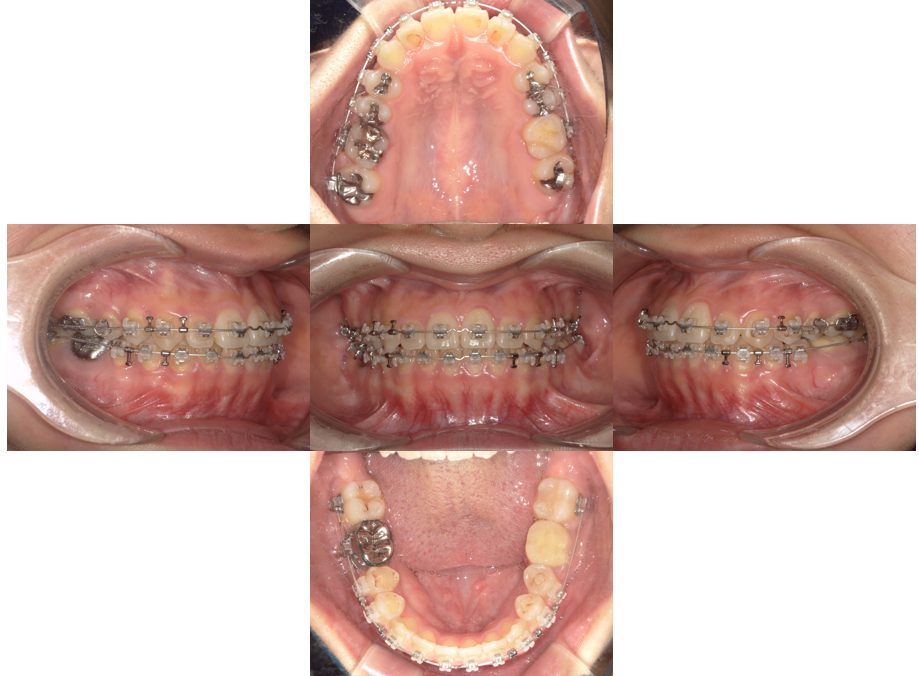

| 主訴 | 20代女性 矯正治療希望。治療途中の歯もあるので治したい。左顎関節が痛い。 |

| 治療内容 | 矯正治療を行いました。 |

| 治療費 | 1,400,000円(税込み) |

| 治療期間 | 3年(矯正治療期間 2年半) |

| 治療回数 | 40回 |

| 想定されたリスク | 顎骨の変形があったので、全身麻酔下による外科処置が必要になり、身体的、精神的負担が増す可能性がありました。 清掃状況によっては矯正中にむし歯が発生するリスクがありました。 |